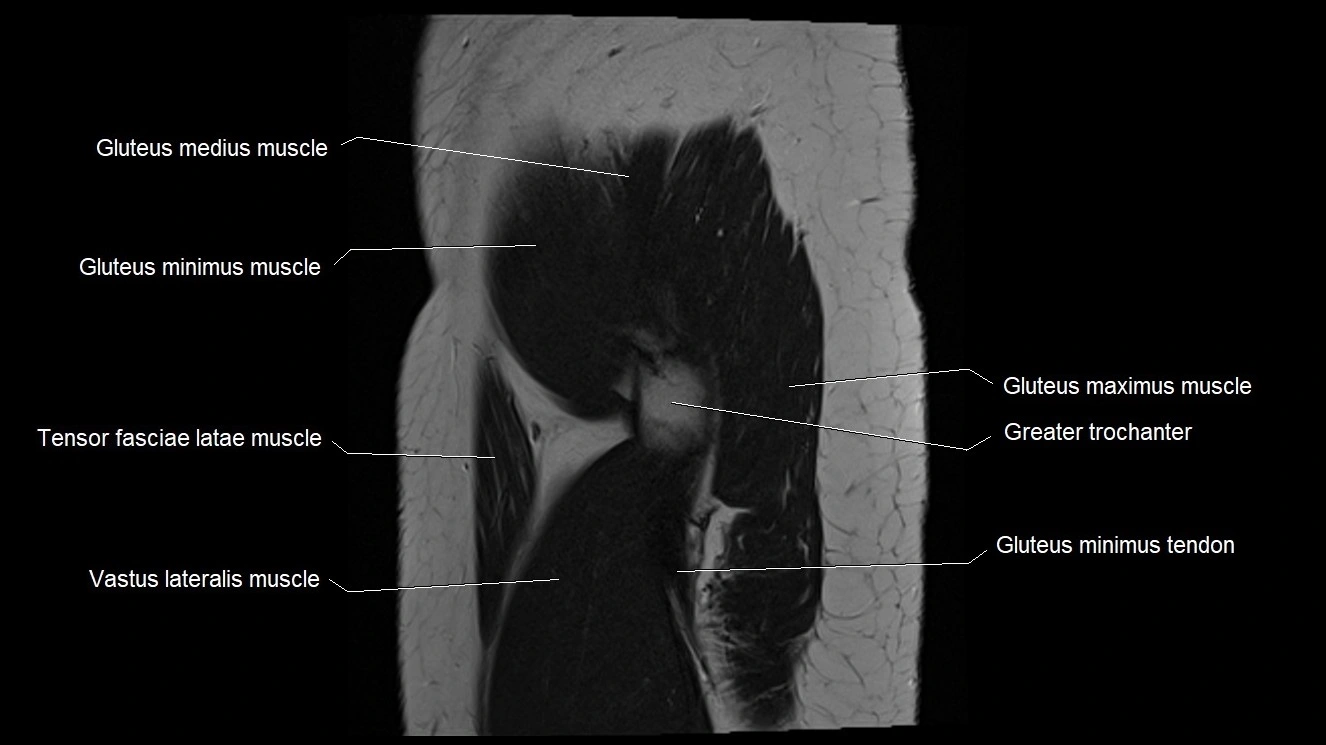

- Gluteus medius muscle

- Gluteus minimus muscle

- Gluteus minimus tendon

- Greater trochanter

- Tensor fasciae latae muscle

- Vastus lateralis muscle